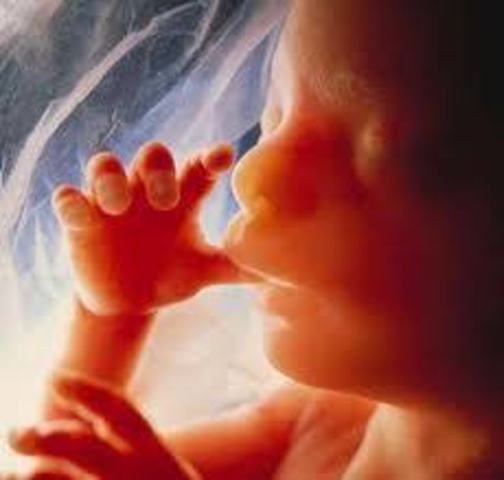

• semana 13 de embarazo

semana 13 de embarazo

A las 13 semanas de embarazo, el bebé está comenzando un período en el que aumentará rápidamente de peso y longitud. Ahora tiene aproximadamente entre 6.5 y 7.5 cm de largo y pesa entre 14 y 21 gramos. Durante esta semana de embarazo las orejas y los ojos se están moviendo hacia su posición. Ya han aparecido los 27 huesos de la mano y pronto el bebé comenzará a chuparse el dedo. Es un momento muy especial, ya lo verás.